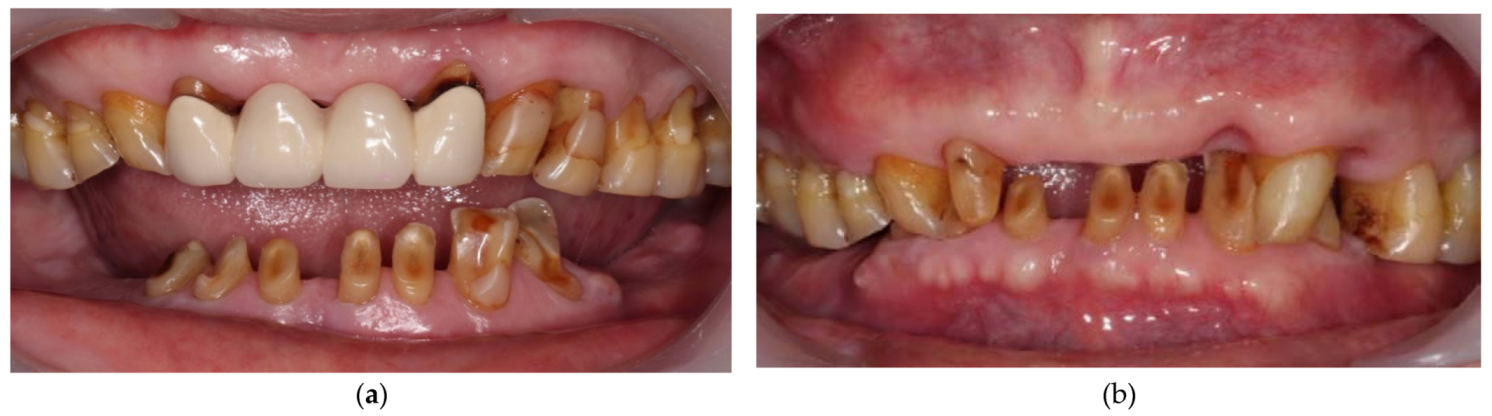

2. Case Description